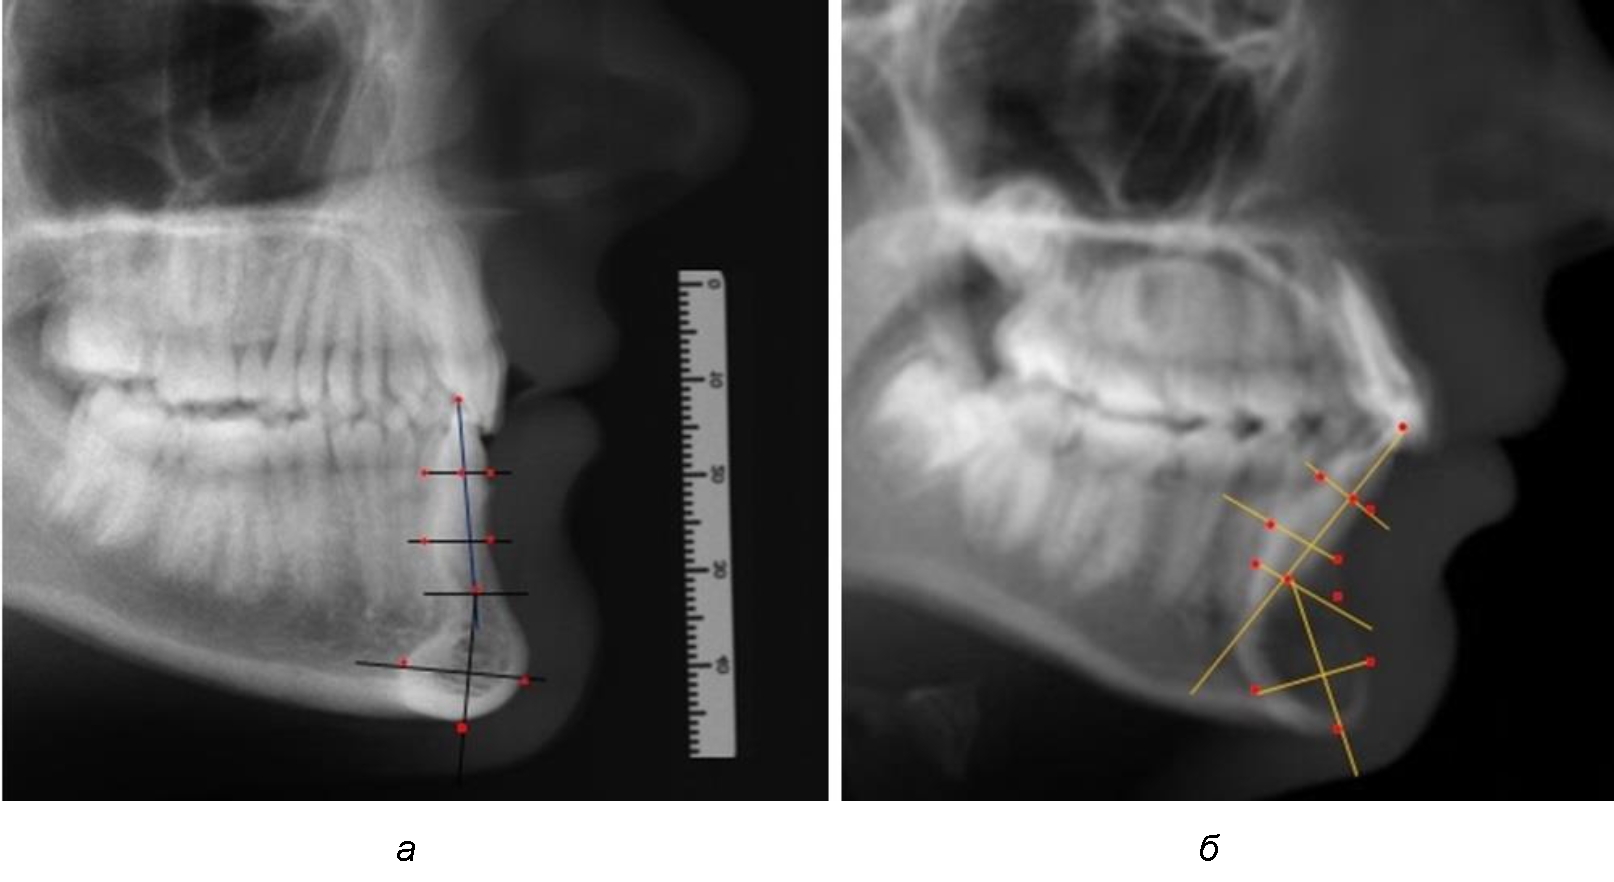

Предложен метод исследования зубочелюстных сегментов, который проводился на масштабированных фотографиях, и в программе Microsoft PowerPoint обозначались точки с последующим построением линий, необходимых для измерения по вертикали и сагиттали.

На режущем крае нижнечелюстного резцового сегмента устанавливалась точка, обозначаемая как IsL.

Определяли положение цервикальных точек резцов на вестибулярной и лингвальной поверхностях, которые соединяли цервикальной линией. Условная срединную вертикаль зуба соединяла резцовую точку IsL с серединой цервикальной линии и, как правило, доходила до апикальной точки, которую обозначали как Ap. Линия IsL–Ap определяла высоту зубоальвеолярной части резцового нижнечелюстного сегмента. Определяли высоту коронки и корня зуба. Кроме того, на вестибулярной поверхности зубочелюстного сегмента отмечали точку наибольшей вогнутости альвеолярной части, которая обозначалась как супраментальная точка Downs (Bsm). Измерялось расстояние IsL–Bsm, которое служило для определения проекции супраментальной точки Downs на язычную поверхность сегмента и обозначалась как точка Bsm'.

Проекцию верхушки корня резца на кость обозначалась как точка B нижнего апикального базиса по Schwarz. Соединяли апикальную точку с точкой нижнечелюстного апикального базиса линией, которая доходила до язычной поверхности подбородочного выступа и определяла положение точки B'. Таким образом, в зубоальвеолярной части сегмента выделялись две зоны: верхняя и нижняя, с последующим измерением по вертикали. При этом, как правило, верхняя зона была представлена компактной костной тканью, а в нижней зоне определялось наличие губчатой ткани между компактной пластинкой и стенкой альвеолы.

На нижнем контуре подбородочного выступа определяли положение ментальной точки Me. Линия, соединяющая апикальную точку с ментальной, определяла высоту подбородочного выступа тела нижней челюсти. Высота зубочелюстного сегмента IsL–Ме измерялась от резцовой до подбородочной точки. Вертикальная линия Ap–Me делила подбородочный выступ на две части: переднюю и заднюю (рис. 1).

Рис. 1. Ориентиры для исследования нативных препаратов (а) и рентгенограмм (б) резцового нижнечелюстного сегмента

Сагиттальные размеры зубоальвеолярной части сегмента определялись между точками Bsm и Bsm', в апикальной части сегмента – B и B'. В подбородочной части сегмента из передней выступающей точки подбородка Pog проводили линию перпендикулярно к линии Ар–Ме с определением точки Pog'. Расстояние Pog–Pog' определяло ширину подбородочного выступа.

При анализе боковых телерентгенограмм использовали фрагменты гнатической части, на которых оценивали вертикальные и сагиттальные параметры резцового нижнечелюстного сегмента, на который наносили те же ориентиры, что и при анализе нативных препаратов и их рентгенограмм.

При необходимости и/или возможности проведения КЛКТ-исследования проводили анализ с сопоставлением фрагмента, что повышало точность диагностических мероприятий (рис. 2).

Рис. 2. Фрагменты ТРГ с ориентирами для измерения параметров резцового сегмента (а) и с наложением фрагмента КЛКТ (б)